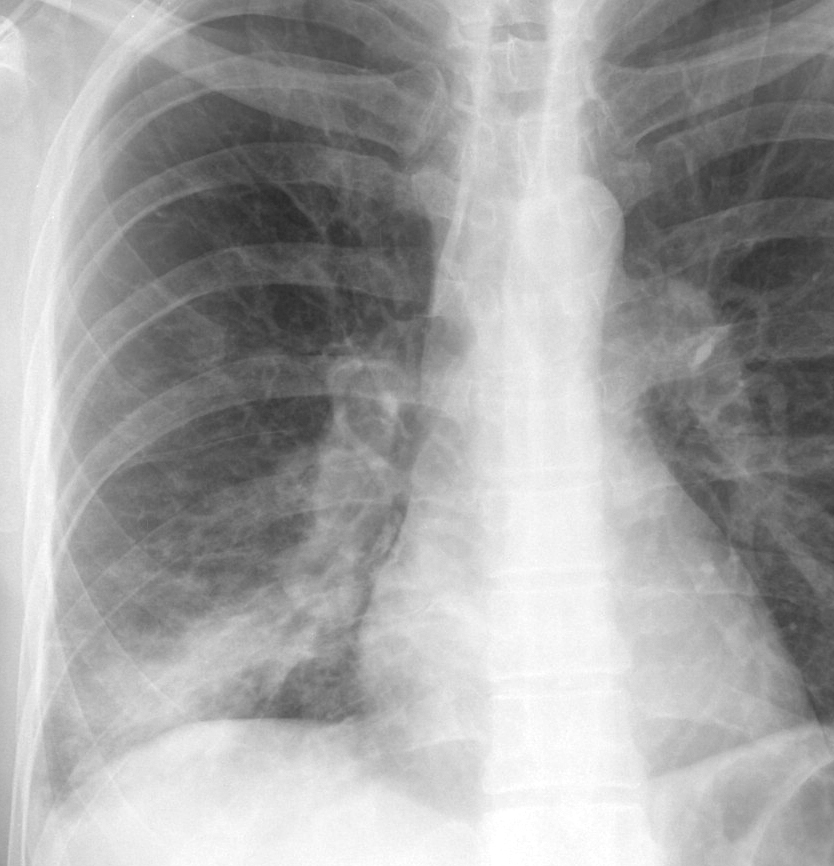

Case 9 RLL brpneum PA

Date: 11/02/2004